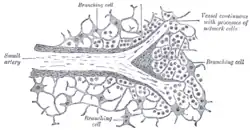

The celiac artery and its branches. Transverse section of the human spleen, showing the distribution of the splenic artery and its branches.

Transverse section of the human spleen, showing the distribution of the splenic artery and its branches. Section of the spleen, showing the termination of the small bloodvessels.

Section of the spleen, showing the termination of the small bloodvessels. Posterior abdominal wall, after removal of the peritoneum, showing kidneys, suprarenal capsules, and great vessels.